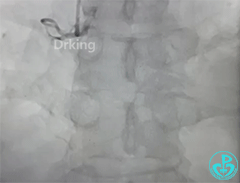

右冠造影:

导丝怎么扩收藏:器械难以通过的CTO病变之技术图谱_https://www.jmylbn.com_新闻资讯_第6张

导丝怎么扩收藏:器械难以通过的CTO病变之技术图谱_https://www.jmylbn.com_新闻资讯_第7张

导丝怎么扩收藏:器械难以通过的CTO病变之技术图谱_https://www.jmylbn.com_新闻资讯_第8张